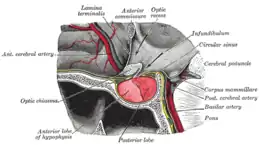

L'hypophyse se trouve dans une cavité osseuse, la fosse hypophysaire qui se situe dans l'os sphénoïde. Elle est protégée par la selle turcique. Elle est reliée à une autre partie du cerveau appelée l'hypothalamus par une tige hypophysaire (également appelée tige pituitaire). Elle produit des hormones qui gèrent une large gamme de fonctions corporelles, dont les hormones trophiques qui stimulent les autres glandes endocrines. Cette fonction lui a valu de se faire appeler par les scientifiques « glande maîtresse » du corps, mais aujourd'hui on sait que l'hypophyse est régulée par les hormones (neuro-hormones) émises par l'hypothalamus.

L'hypophyse est divisée en deux lobes : l'antéhypophyse (adénohypophyse) en avant, et la posthypophyse (neurohypophyse) en arrière. L'adénohypophyse dérive du plafond de la cavité buccale primitive (stomodeum), tandis que la neurohypophyse est une extension de l'hypothalamus, relié à celui-ci par la tige pituitaire, et contient les axones de neurones dont les corps cellulaires se trouvent dans l'hypothalamus. On peut également trouver entre l'antéhypophyse et la posthypophyse, une troisième structure, l'hypophyse intermédiaire, bien développée chez certaines espèces animales[Lesquelles ?] : chez l'humain, l'hypophyse intermédiaire (pars intermedia) est seulement visible en période fœtale et jusqu'à l'âge de dix ou vingt ans ; chez l'adulte, il subsiste quelques structures kystiques (follicules, restes de la poche de Rathke), ainsi qu'un infiltrat chromatophile basophile.

L'antéhypophyse est en relation avec l'hypothalamus et les relations sanguines entre les deux glandes se font par le biais du système vasculaire porte hypothalamo-hypophysaire, qui permet le transport des neurohormones sécrétées par l'hypothalamus. Elle entre donc en jeu dans plusieurs axes de signalisations biologiques, comme l'axe gonadotrope.

La posthypophyse ou neurohypophyse (ou lobe postérieur, pars nervosa) est en fait une projection de l'hypothalamus, elle consiste en une agglomération d'axones projetés par les noyaux contenant les corps cellulaires des neurones. Ces neurones sont en contact (par leur cylindraxe) avec des capillaires sanguins entrant par l'artère hypophysaire inférieure et sortant par la veine hypophysaire. Ces bourgeons terminaux axonaux sont dénommés Corps de Herring. Les axones vont sécréter dans ces capillaires sanguins le contenu des granules de sécrétion qu'ils contiennent, qui vont libérer les deux neurohormones qui sont sécrétées au niveau de la neurohypophyse, soit la vasopressine et l'ocytocine. Elle ne produit pas ses propres hormones ; elle ne fait qu'entreposer et distribuer les hormones ocytocine et vasopressine sous forme de neurosécrétions.